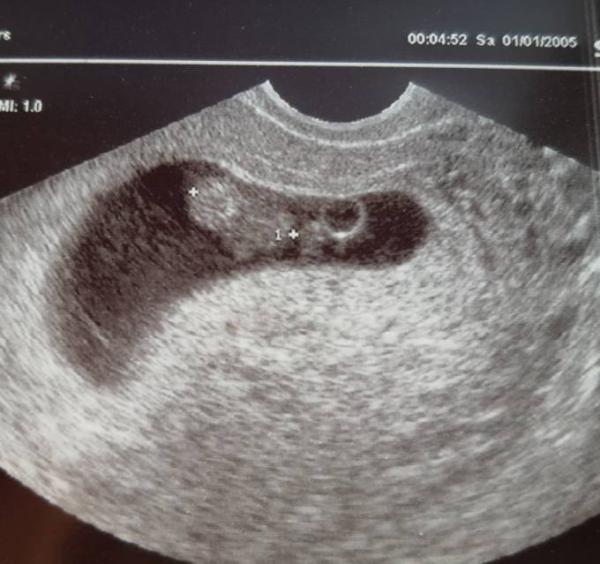

Wie süß, dass du fragst :) Es war ein ganz wundervolles kleines gummibärchen. Nur in Bewegung. Daher war kein wirklich schönes Bild zu erhaschen. Aber das ist so egal Alles dran!!!! Und ich finde es sieht aus ein Junge Warum auch immer ich das glaube...